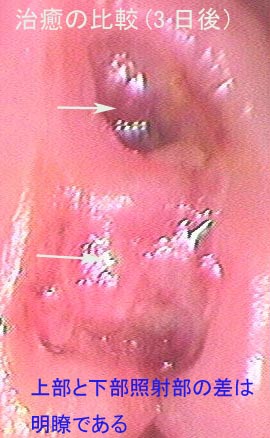

4.レーザー治療の症例

以下のレーザー治療の症例はレーザー照射の対象組織が量子生物学的、あるいは量子化学的な変化によって短時間に治癒した状態を示しています。なお、これらの症例以外に、レーザーによる治療効果はHPの他のコンテンツにも含まれていますのでご参照下さい。